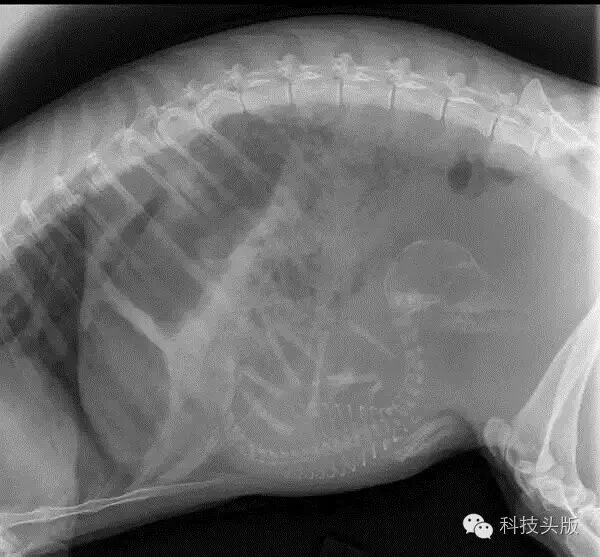

这是一只怀孕的狗狗,鼓囊囊的满肚子里都是小生命。